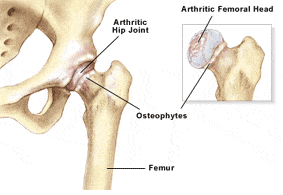

Osteoarthritis, also called degenerative joint disease is the most common form of arthritis. It occurs most often in older people. This disease affects the tissue covering the ends of bones in a joint (cartilage).In a person with osteoarthritis, the cartilage becomes damaged and worn out causing pain, swelling, stiffness and restricted movement in the affected joint. This condition most commonly affects the joints in hips, knees, hands, and spine. Rarely, the disease may affect the shoulders, wrists and feet.

The term Arthritis literally means inflammation of a joint, but is generally used to describe any condition in which there is damage to the cartilage. Inflammation is the body's natural response to injury. The warning signs that inflammation presents are redness, swelling, heat and pain.

The cartilage is a padding that absorbs stress. Usually the pain early on is due to inflammation. In the later stages, when the cartilage is worn away, most of the pain comes from the mechanical friction of raw bones rubbing on to each other.